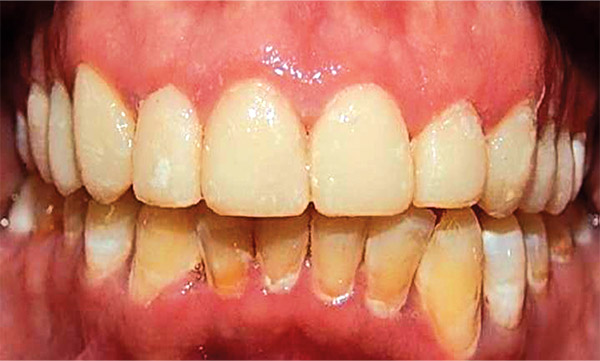

En las fotografías intraorales se muestra la fluorosis dental Tf4 y Tf7, las relaciones molares clase II molar y canina bilateral (Figura 3 y 4), el apiñamiento severo superior e inferior, con el órgano dental 35 en infraoclusión. El overbite aumentado y las líneas medias dentales no son coincidentes (Figura 5), las formas de arco superior e inferior son cuadradas (Figura 6 y 7).

Figura 5. Frente.

Se observa en las fotografías intraorales la mecánica utilizada con los brackets y al paciente con mejor alineación y nivelación dental (Figura 12-14).

Figura 13. Frente.